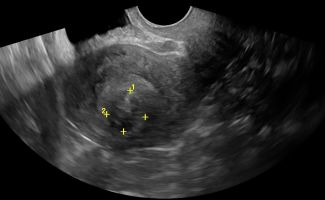

- Ωοθήκες: Η απεικόνιση των ωοθηκών περιλαμβάνει την αξιολόγηση του μεγέθους, της μορφολογίας και της υφής τους. Με το Διακολπικό Υπερηχογράφημα, μπορούν να μετρηθούν τα ωοθυλάκια και να διερευνηθεί η παρουσία συνδρόμου πολυκυστικών ωοθηκών. Οι εστιακές βλάβες στις ωοθήκες, συμπαγείς ή κυστικές, μπορούν να αξιολογηθούν ως καλοήθεις ή ύποπτες, με τη βοήθεια του Έγχρωμου Doppler για την απεικόνιση της αγγείωσης και της ροής του αίματος.